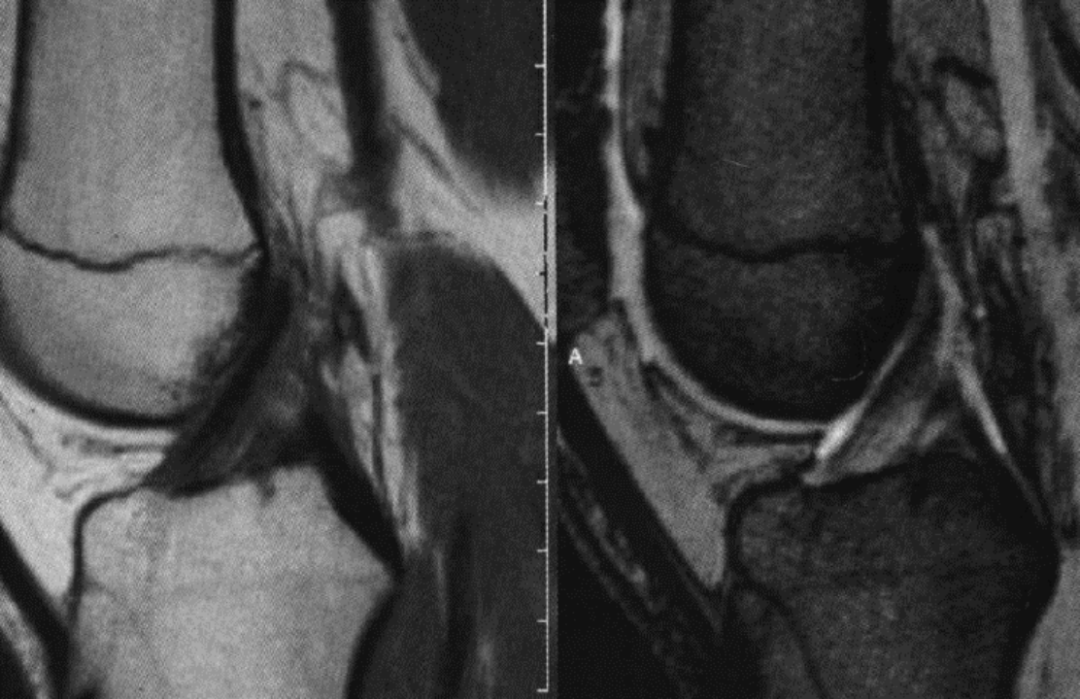

正常前交叉韧带的MR表现:

为前缘界限清晰的直线走向纤维束信号。

当纤维束致密时,MR 图像为界限清晰带状低信号。

当纤维束呈扇形走向,MR 图像可以表现为中等信号。

前交叉韧带中段的直径较两端细。